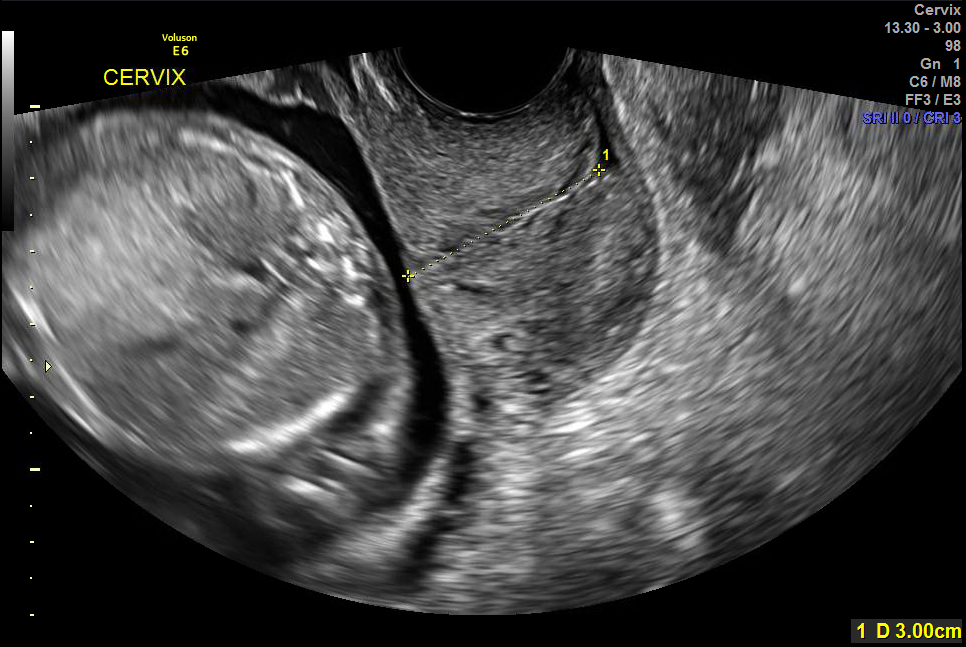

- Women with a measured (Normal) CL ≥ 25mm were compared to those with PDLUS.

Figure 2. Measured normal cervical length.